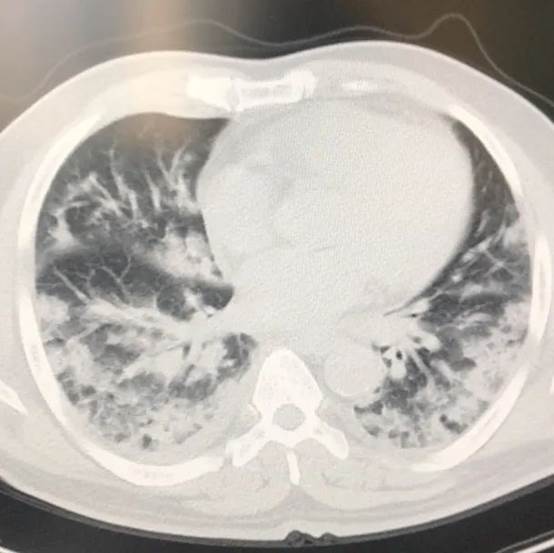

“患者当时已经是呼吸衰竭的状态,我们第一时间给上了呼吸机。”ICU主任郑孝敬说,CT检查显示患者两肺大面积感染,血氧饱和度仅为75%(正常值应在95%以上)。

1月3日 CT影像